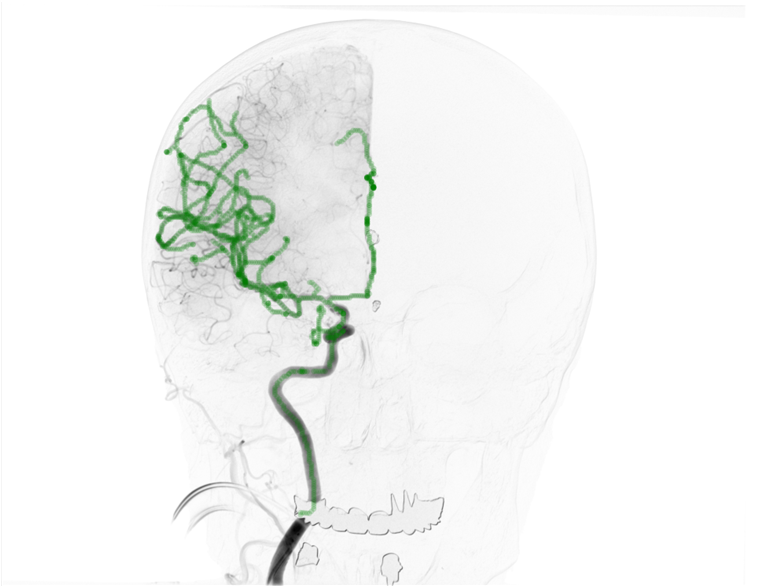

3.3.2 Evaluation on public datasets

Other than our local endoleak dataset, two public clinical datasets (i.e., 3D-2D-GS-CA and DeepFluoro) were used to evaluate the generalization of our fluoro-CT registration workflow.

3D-2D-GS-CA: This dataset includes images from 10 patients who underwent cerebral-endovascular procedures, with 8 cases focused on aneurysm treatment and 2 on arteriovenous malformation. All images were acquired intraoperatively just prior to treatment. For each patient, a 3D digitally subtracted angiogram (3D-DSA) with vessel contrast was acquired, which had voxel sizes of \qtyproduct0.46 x 0.46 x 0.46\milli and image sizes of 512 512 391 pixels. In addition, two 2D fluoroscopic (2D-Fluoro) and two 2D-DSA images were acquired from lateral and the AP views, with pixel sizes of \qtyproduct0.15 x 0.15\milli and image sizes of either 1920 2480 pixels or 2480 1920 pixels. 2D-Fluoro images have lower vessel contrast and display nonvascular anatomical structures and interventional tools, in contrast to 2D-DSA images. All 2D-3D image pairs have ground-truth extrinsics, intrinsics and target points, as described in the work of Mitrovic et al. [31]. Only the AP views (2D-DSA and 2D-Fluoro) were used to test our fluoro-CT registration approach.

Table 4 summarizes the registration errors for the 3D-2D-GS-CA and DeepFluoro datasets. Both datasets achieved similar 2D registration errors, with mPDs and mRPDs approximately . For 3D, 2D-Fluoro cases yielded a mean TRE of , though 2 out of 10 cases had mTREs exceeding . Fig. 8 shows qualitative results for 8 cases, showing input fluoroscopy/DSA, the registered image, and the input fluoroscopy/DSA with post-registration target points overlaid. All cases demonstrated good alignment, particularly in cases C-1 and C-2, underscoring the approach’s effectiveness.